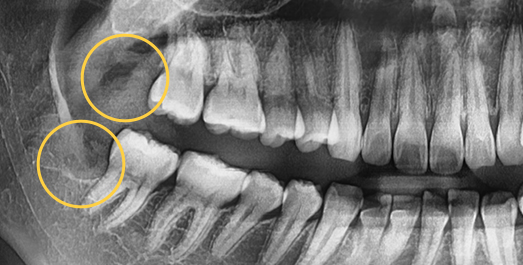

Even advanced cases

can be extracted.

With extensive experience in numerous advanced cases and a wide range of wisdom tooth extractions, you no longer need to go to a university hospital.

• BEFORE

• AFTER

Treatment Date : 2024.09.04

Treatment Date : 2023.12.22

Treatment Date : 2024.05.28